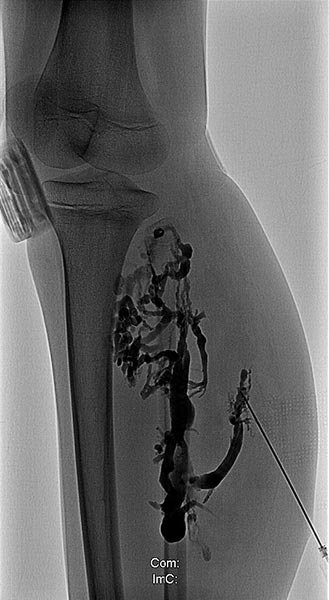

Die Phlebographie nach Direktpunktion des venösen Malformationsanteils zeigt eine großlumige Drainagevene, die in der Kniekehle mit der V. poplitea kommuniziert. Diese muss zunächst verschlossen werden, da sonst das Sklerosierungsmittel darüber abfließen könnte und potentiell eine Thrombose der tiefen Leitvenen des Beins (und eine Lungenembolie) verursachen könnte. Zudem besteht grundsätzlich ein erhöhtes Thrombembolierisiko bei der Patientin, dass durch den Verschluss deutlich vermindert werden kann.

Dazu wird zunächst über einen Einführungsdraht eine großlumige Einführungsschleuse vorgebracht, die zum Einführen der Laserfaser dient. Dieser wird über die Vene bis zum Kommunikationspunkt in der Kniekehle vorgeschoben.

Durch diese Schleuse wird eine Laserfaser zur endovaskulären Lasertherapie vorgeführt. Durch die Erhitzung des Laserstrahls kommt es zu einer massiven Reizung der Venenwand, die sich anschließend sehr schnell verschließt. Um die Laserspitze kommt es sofort zur Thrombusbildung (weiß, da als Kontrastmittelaussparung sichtbar).

Nach Verschluss durch die Laserfaser und Anspritzen über die zurückgezogene Schleuse kommt es nicht mehr zu einem Abstrom des Kontrastmittels über die Kommunikationsvene, die erfolgreich verschlossen ist. Es kontrastiert sich nur noch die venöse Malformation. Diese ist jetzt bereit zur Sklerosierungsbehandlung, da dieses nicht mehr abfließen kann.

Auch nach zusätzlicher Punktion des ganz distalen Anteils der großlumigen Kommunikationsvene zeigt sich kein Abstrom mehr ins tiefe Leitvenensystem. Somit ist auch im Langfristverlauf die Gefahr gebannt, dass es zur Embolie von Thromben aus der venösen Malformation in zentrale Venen kommt.